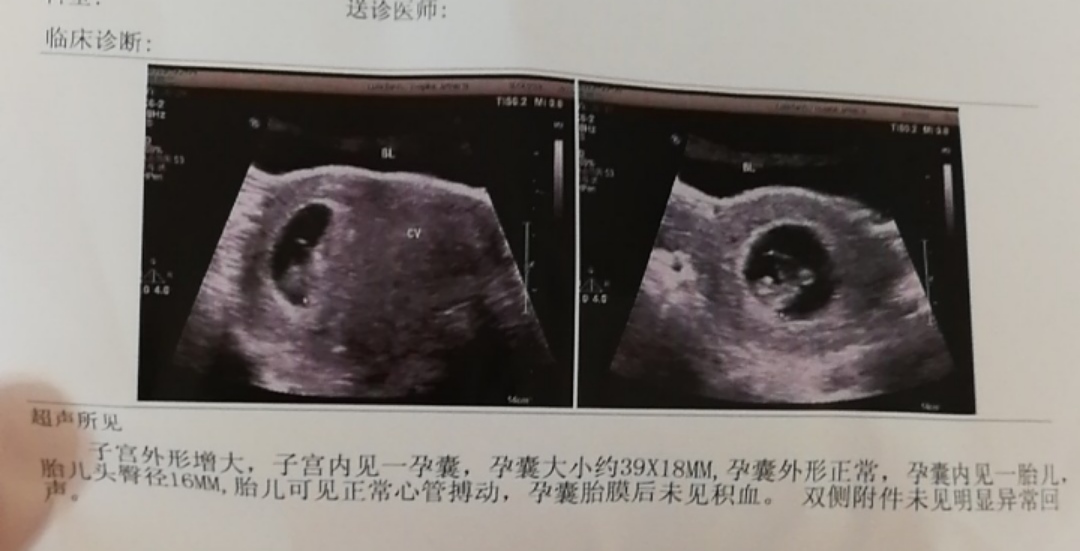

Anna[帖主]:不是说早期孕囊看形状可以看得出来吗?